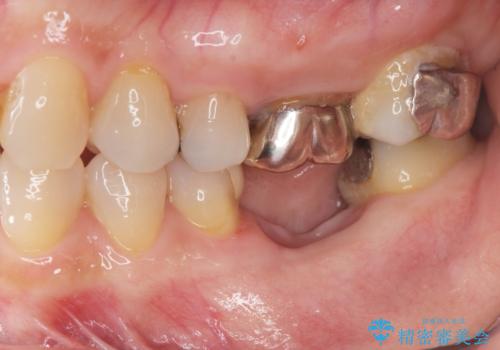

- 他院で行われた抜歯後の機能回復について相談に来院されました。

インプラント治療、入れ歯と比較し、前後の銀歯や詰め物の問題も一緒に治療のできるブリッジ治療を選択されました。

ブリッジは早期に審美性・機能性を回復できる治療法です。